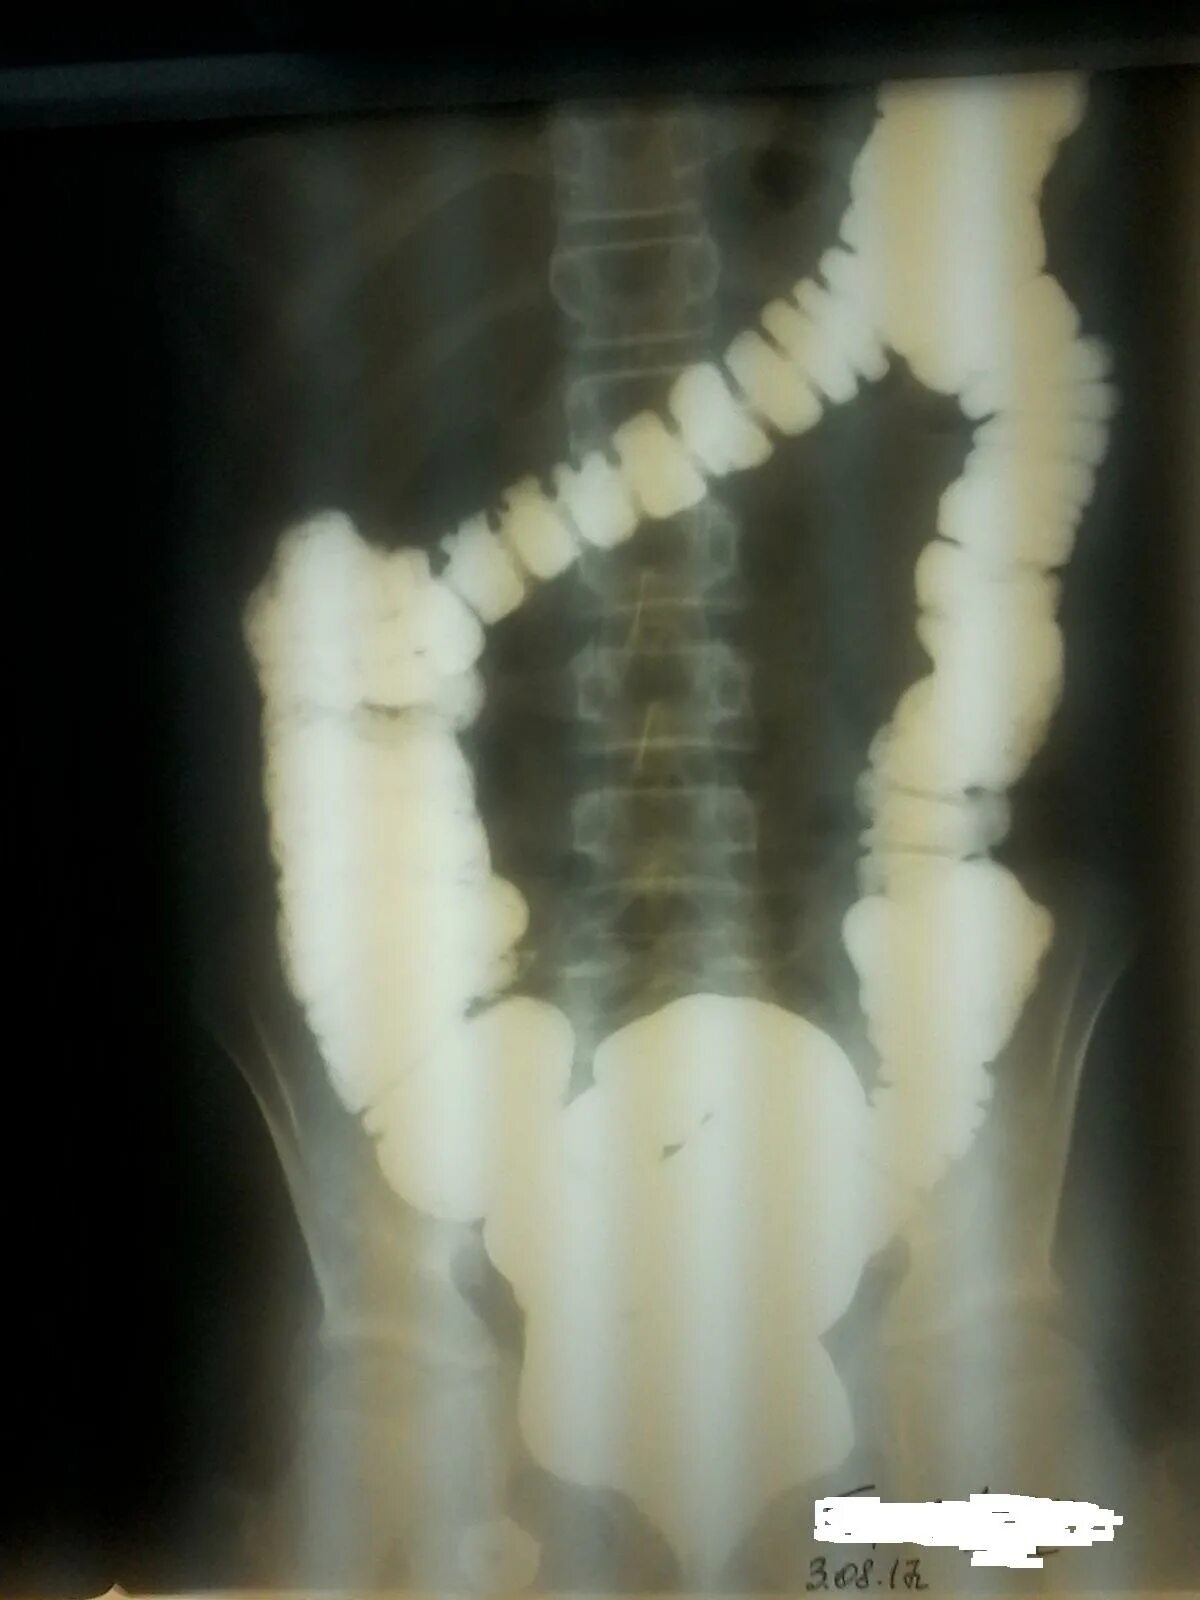

Долихоколон симптомы у взрослых